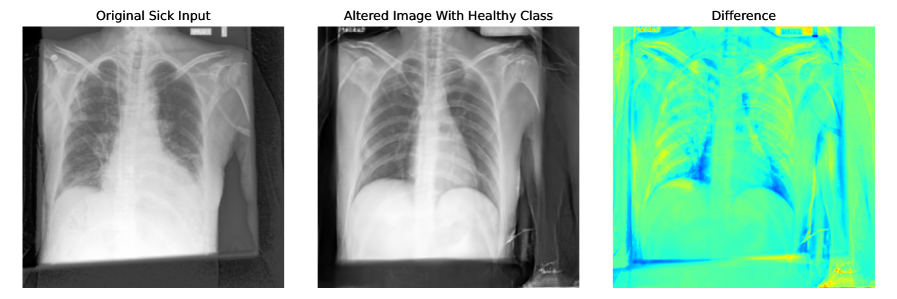

Appendix E More Explainability Results

More explainability results can be found in Figure 6, and Figure 7. Input sick images have been altered to healthy class by adding noise to the input image and denoising with the healthy class. For CheXpert t=0.5 and for ISIC t=0.3 are used. CFG scale is 7.5.

Refer to caption

Figure 6: More explainability results for CheXpert by converting input sick images to healthy images. t=0.5 and CFG=7.5 are used for generating these images.